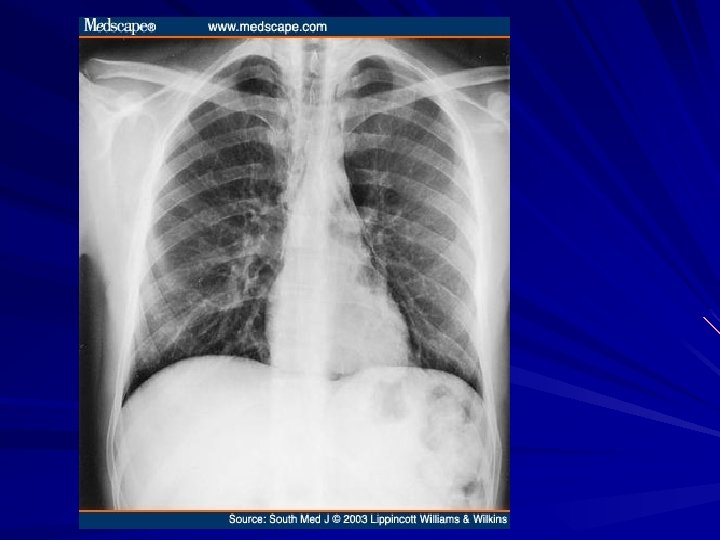

Diagnosis CXR may show air-fluid level Barium study quite dilated, and an airfluid level may be secondary to retained secretions. The classic finding is a gradual tapering at the end of the esophagus, similar to a bird's beak Upper endoscopy is the next diagnostic test in a patient with dysphagia or suspected achalasia

GASTROESOPHAGEAL REFLUX DISEASE GERD is often associated with a hiatal hernia the most common is the type I hernia, also called a sliding hiatal hernia Type II and III hiatal hernias are often referred to as paraesophageal hernias and they may be associated with GERD Type IV when there is other organ herniated into the chest (Spleen , Colon)